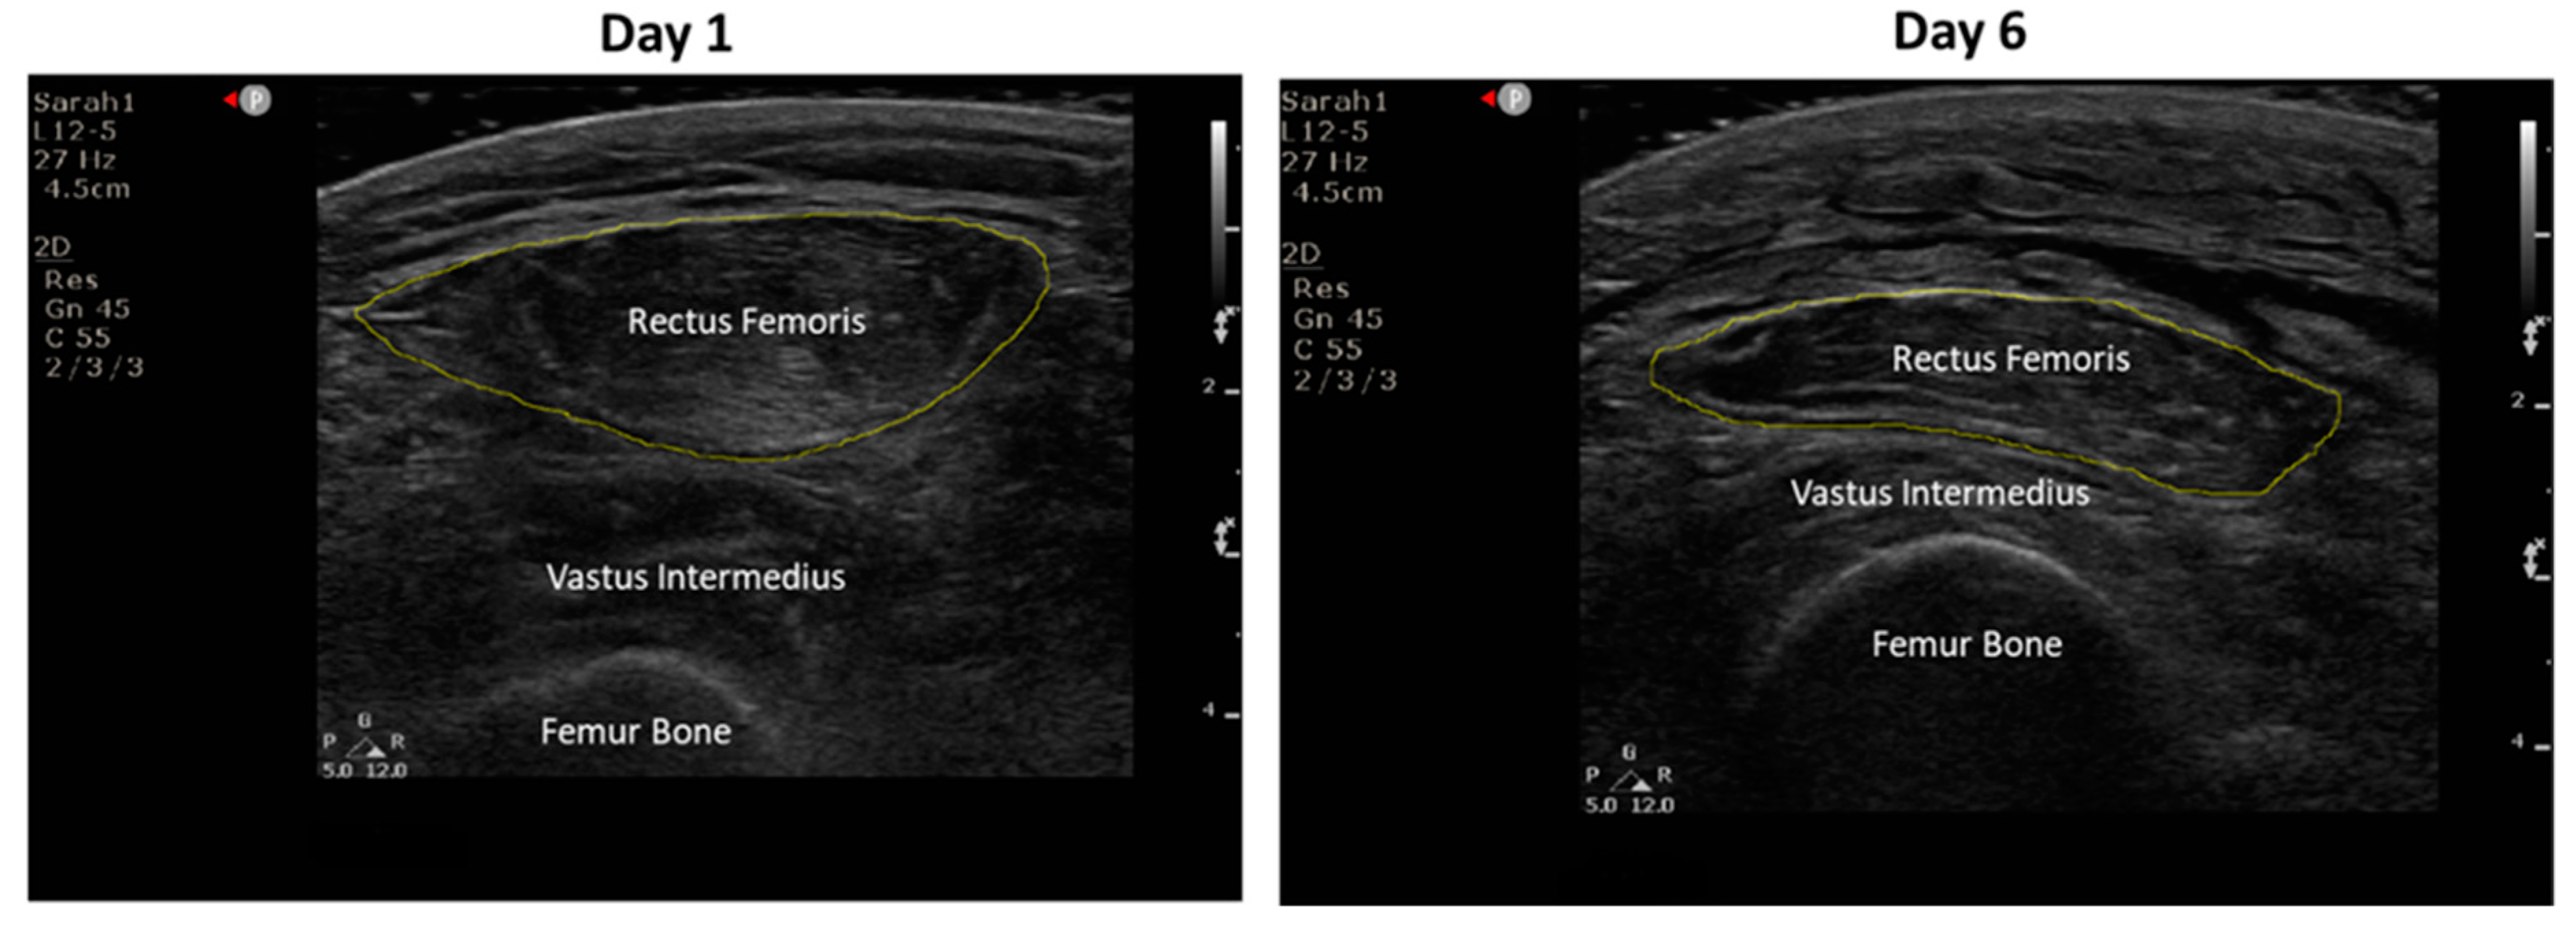

3.4.1. Effect on Rectus Femoris Cross-Sectional Area and Echogenicity

| Outcome Measure Assessments | 100% of RFCSA ultrasound measurements were performed within 24 h of the scheduled time | 100% | |